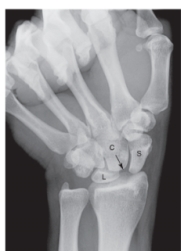

2

-Refer to the figure. Assess the geography of the wrist. This patient has:

A) Negative ulnar variance

B) Positive ulnar variance

C) Neutral ulnar variance

Negative ulnar variance

3

-Carpal alignment is assessed by

A) Ulnar and radial deviation views

B) Clenched-fist functional view

C) Inscribing three arcs on PA view

D) Cineradiography

Inscribing three arcs on PA view